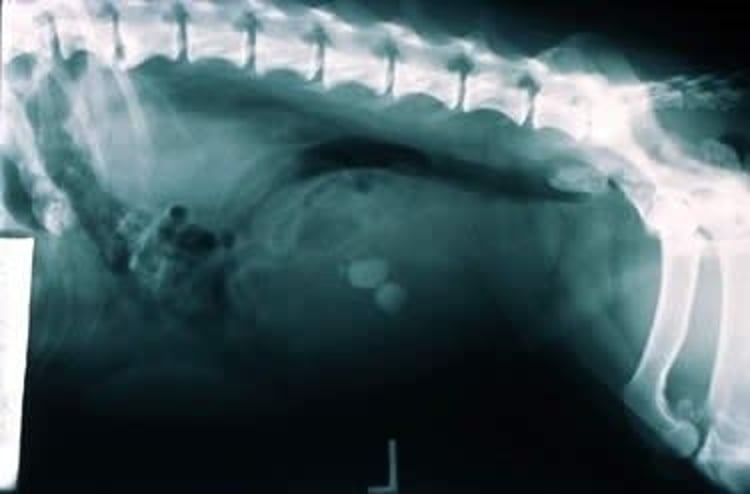

Cálculos de estruvita en la vejiga, radiografía, Teckel

Radiografía lateral de un Teckel de 4 años con urocistolitiasis por cristales de estruvita. Obsérvense las múltiples opacidades minerales lisas y redondas en la vejiga urinaria.

Cortesía del Ontario Veterinary College.